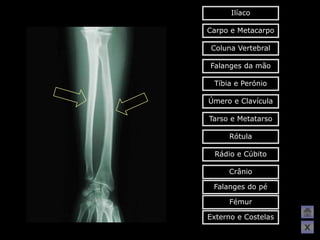

Ilíaco

Carpo e Metacarpo

Coluna Vertebral

Falanges da mão

Tíbia e Perónio

Úmero e Clavícula

Tarso e Metatarso

Rótula

Rádio e Cúbito

Crânio

Falanges do pé

Fémur

Externo e Costelas